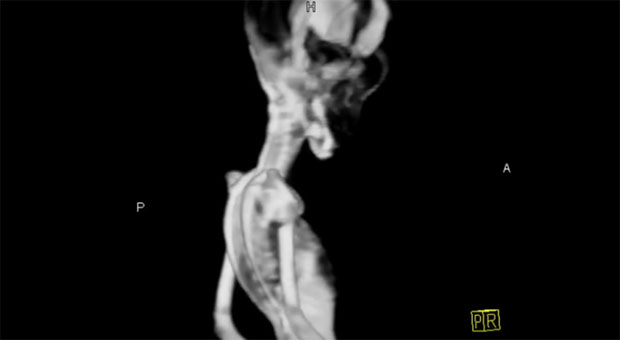

Misterija o mumiji koja je pronađena u napuštenom rudarskom gradu La Noria u pustinji Atakama u Čileu, napokon je rešena.

Iako se u početku mislilo da je reč o stvorenju “vanzemaljskog” porekla, nakon 15 godina od njenog pronalaska naučnici su utvrdili da se radi o devojčici sa nekoliko mutacija gena.

Pronađena mumija je bila veličine fetusa, ali na osnovu urađenih testova utvrđeno je da su kosti pripadale detetu starom između šest i osam godina.

Rezultati testova urađenih na mumiji, nazvanoj Ata, pokazali su da procenjena starost kostiju i druge anomalije predstavljaju urpavo rezultat genetskih mutacija, prenosi “Bi-Bi-Si”.

Njena veličina, ali i oblik glave kao i manjak rebara, godinama su budili sumnje o njenom poreklu. O mumiji je snimljen i dokumentarni film u kome naučnici tvrde da bi ostaci mogli biti dokaz da su Zemlju posetili vanzemaljci.

„Bilo nam je čudno što su kosti izgledale kao da pripadaju starijem detetu po gustoći i obliku. Sada verujemo da je za to odgovoran jedan od mutiranih gena“, rekao je Geri Nolan, profesor mikrobiologije i imunologije s medicinskog fakulteta na univerzitetu Stanford u Kaliforniji.